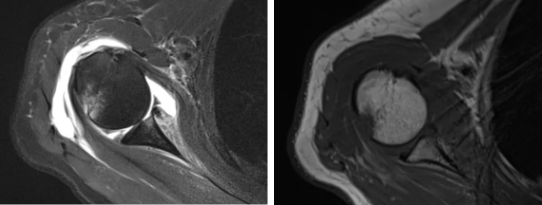

病例2

病史摘要:女性,65歲,跌傷致右肩活動受限9天。

CT圖示:右側(cè)肱骨頭后上部局部明顯凹陷,局部骨皮質(zhì)欠光整(箭頭),外緣見小片狀骨碎片影;右側(cè)肱骨頭向下方移位,關(guān)節(jié)間隙增寬;前下盂唇骨質(zhì)不連續(xù),見多發(fā)小碎骨片影并游離(三角形)。